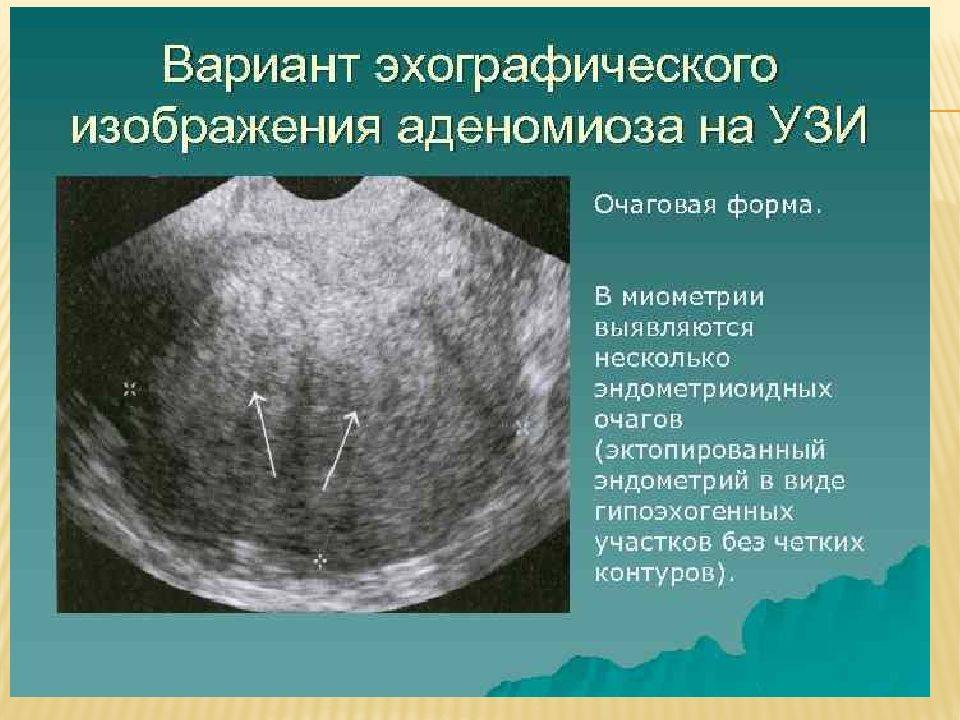

Медицинская диагностика: Гиперплазия эндометрия на УЗИ